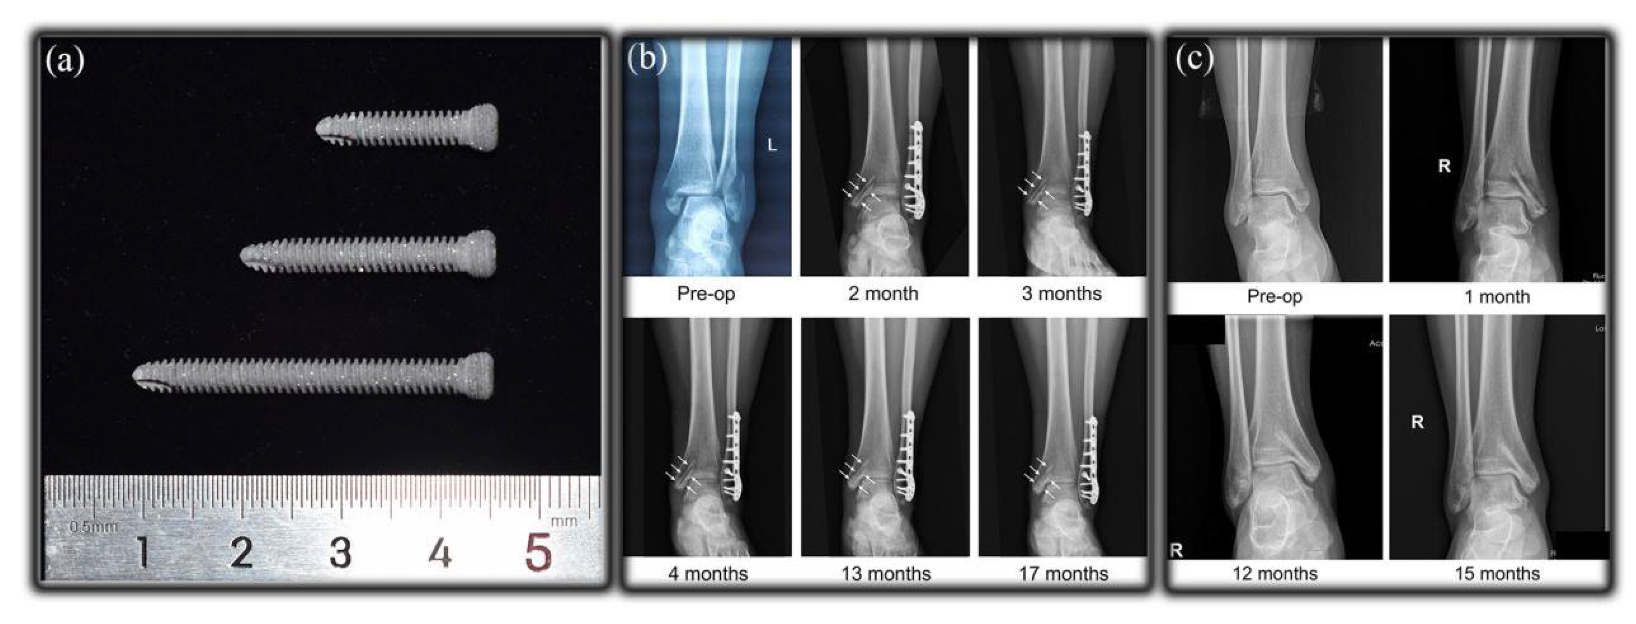

3.2. Bone Screw